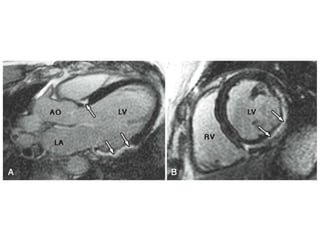

• #81 47 year-old man with no prior medical history presented with dizziness and a junctional rhythm with frequent premature ventricular contractions on a resting electrocardiogram. CMR revealed mildly reduced LV systolic function with akinesis of the basal and midinferior and inferolateral walls. LGE images (A, long axis; B, short axis) demonstrate midmyocardial and epicardial LGE (arrows). In A, apart from the inferolateral midwall enhance- ment (bottom arrows), there was a second focus of LGE seen in the basal septum (top arrow). This pattern of midmyocardial and epicardial LGE is consistent with an infiltrative process, such as sarcoidosis. AO = aorta; LA = left atrium; RV = right ventricle.